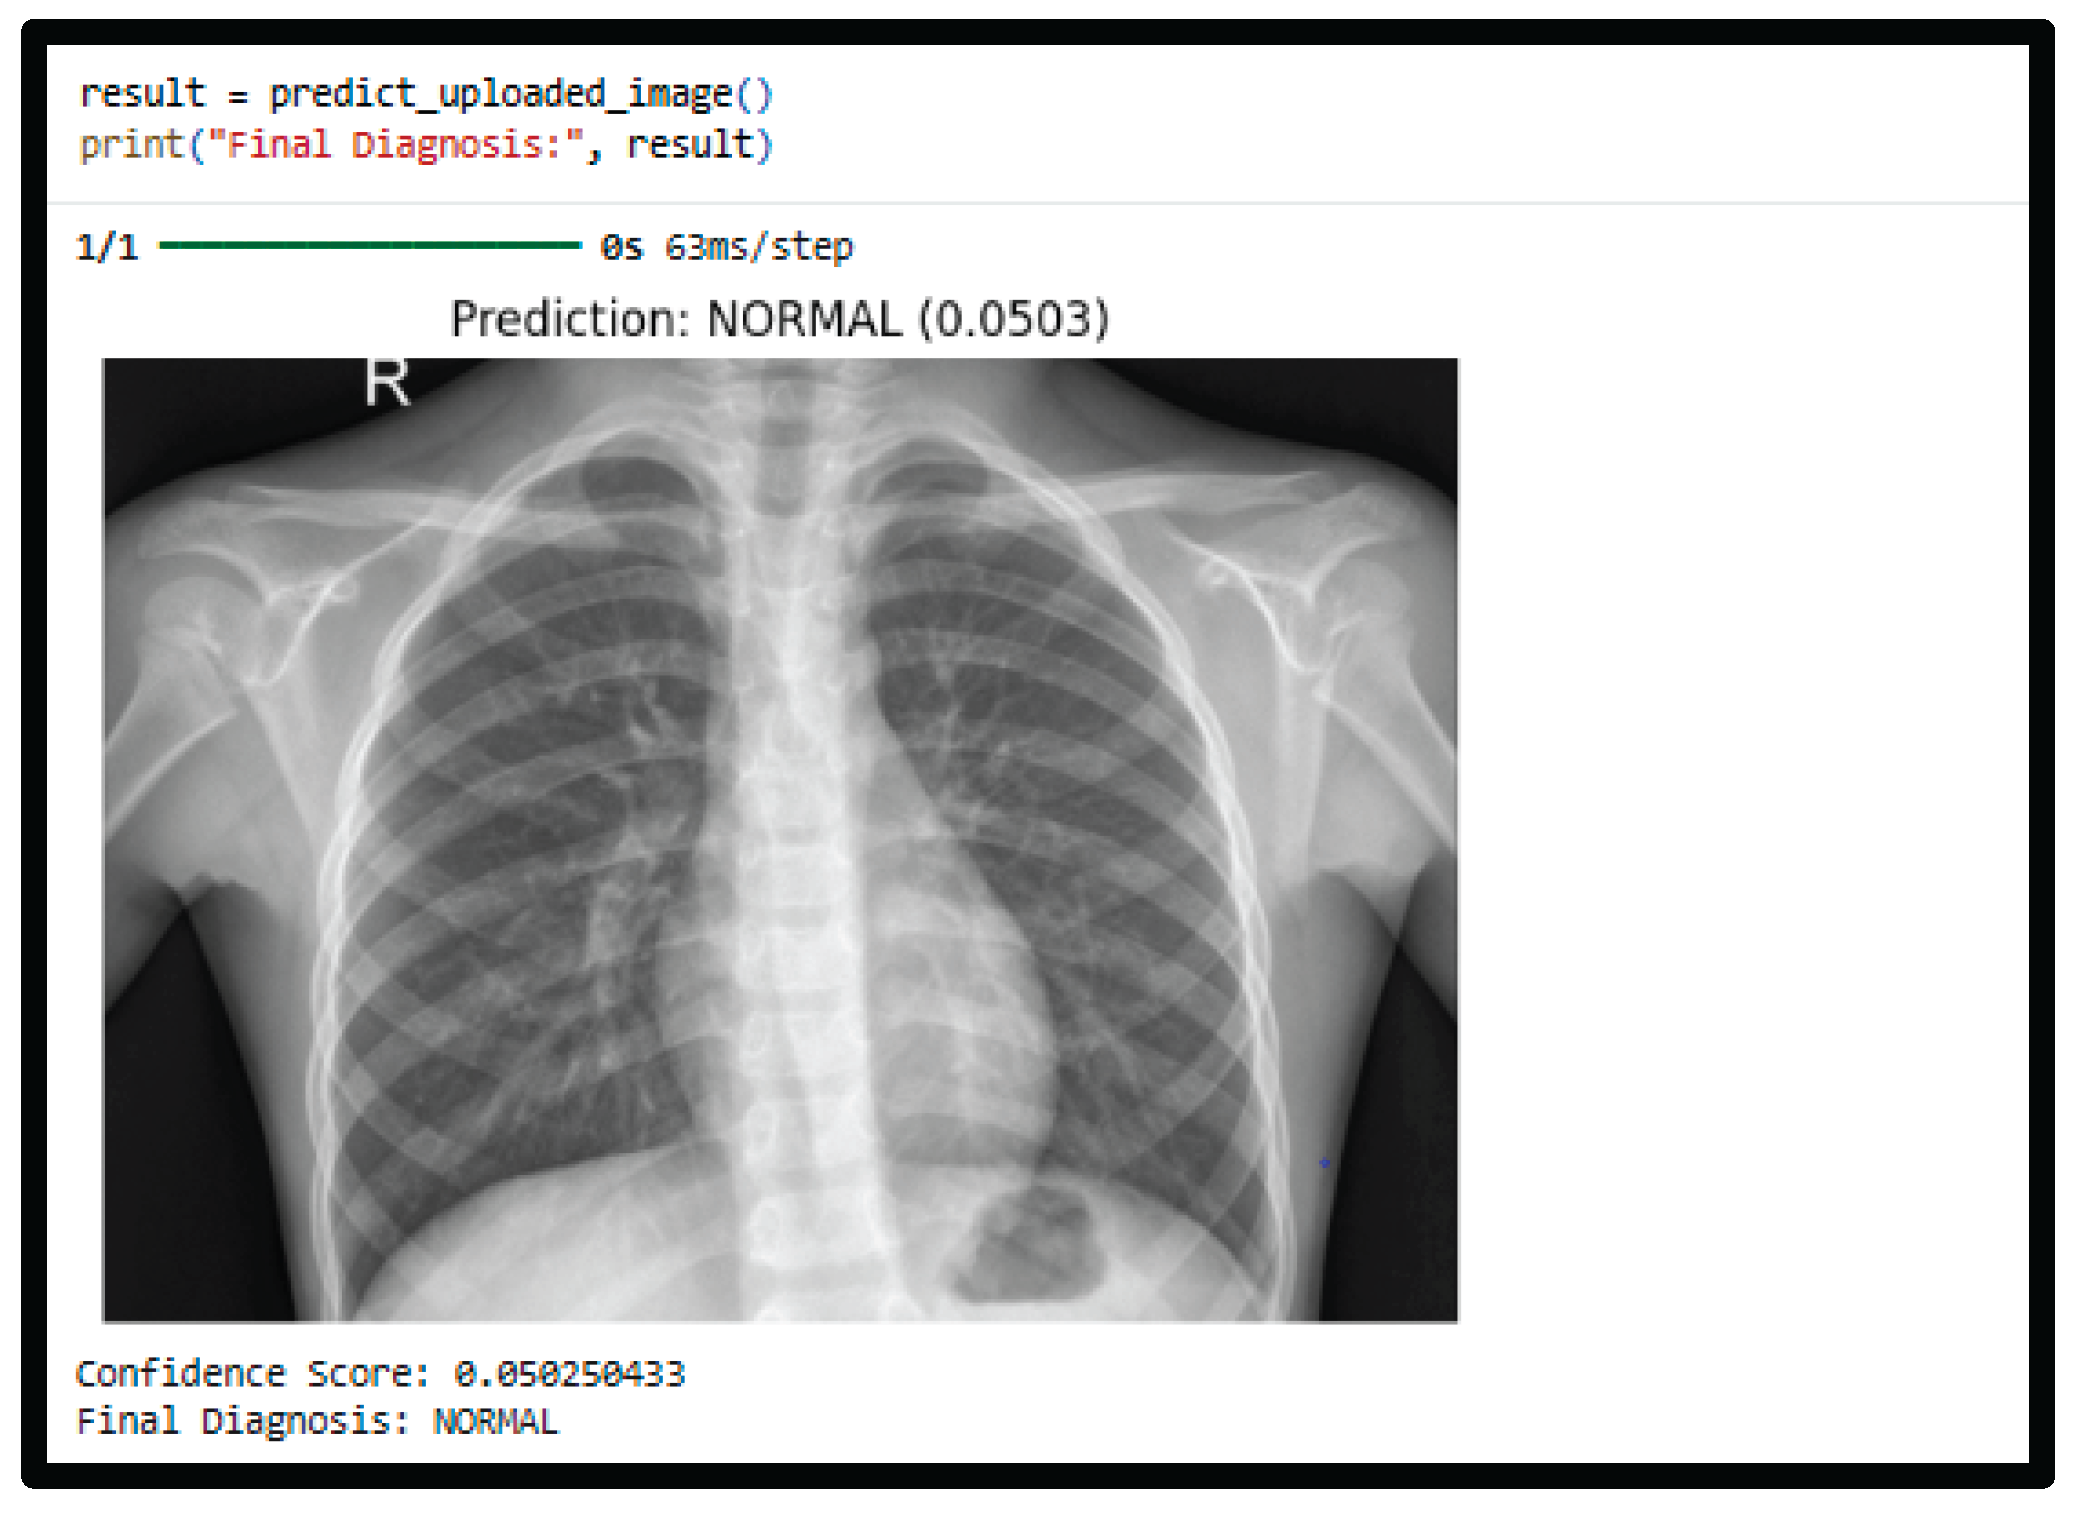

4.4. Prediction Example